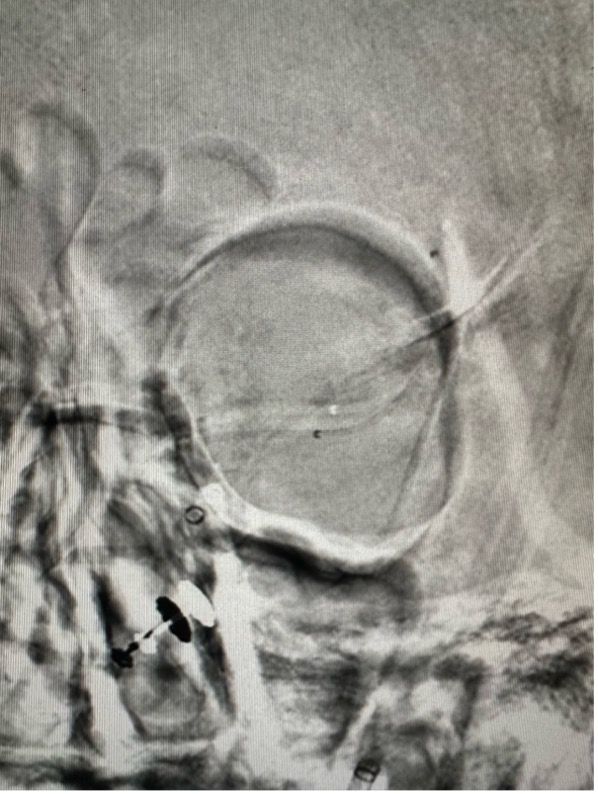

First-in-Human SEAL Aneurysm Device Trial

Conducted the first-in-human SEAL device trial treating 8 patients with complex brain aneurysms (with 18 additional patients treated in a follow-up registry). Zero complications. Results were recognized by the US FDA, paving the way for a larger USA trial.